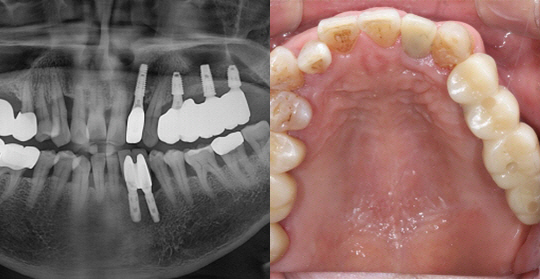

(50세 남 환자)